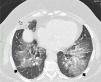

High resolution computed tomography scan of the chest shows peribronchial fat consolidation in middle lobe (white arrows). Extensive representation of GGO containing subtle reticulation (crazy paving) up to pleural spaces (black arrows) 8 months after discontinuing petroleum jelly (Vaseline) and steroid therapy (prolonged for 6 months).